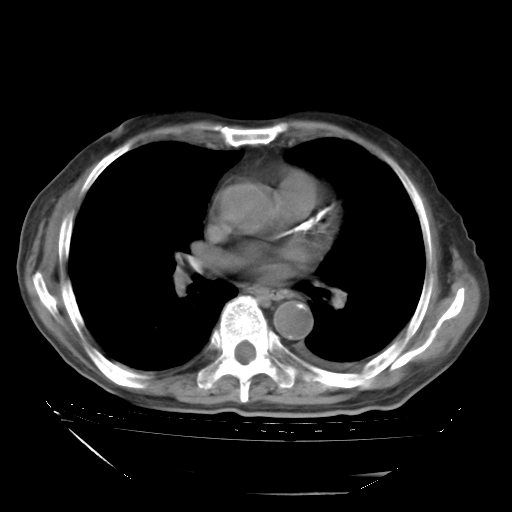

甲强龙80mg/日+抗结核治疗(异烟肼+利福霉素+乙胺丁醇)10天。复查肺部CT。

治疗10天肺部CT